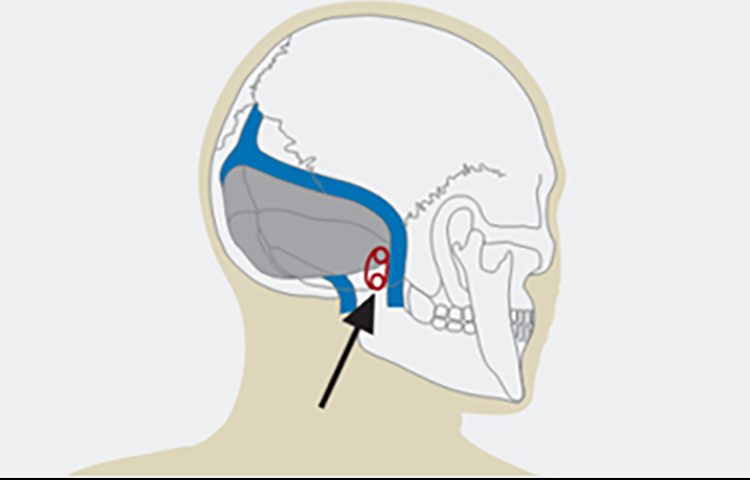

微血管减压术在面肌痉挛患者中的应用

微血管减压术在面肌痉挛患者中的应用

总结背景:面肌痉挛是一种运动性神经紊乱,表现为面部神经所支配的肌肉发生短暂的或持续的无意识收缩。发病率约为11/十万人。